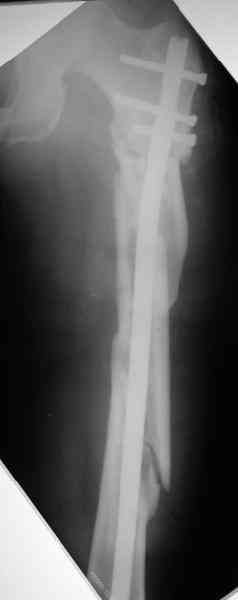

Надо делать чрескожную подвертельную остеотомию, чтобы получился открытый клин. Проблемы будут и с формированием канала, надо развертки типа наших. Был как-то похожий случай, сделали одномоментно, сняли аппарат 5-месячый на столе, заштифтовали с подвертельной остеотомией (в приложении).